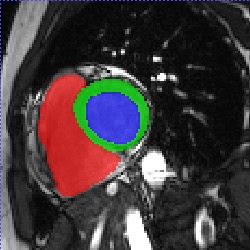

Transformers, the default model of choices in natural language processing, have drawn scant attention from the medical imaging community. Given the ability to exploit long-term dependencies, transformers are promising to help atypical convolutional neural networks (convnets) to overcome its inherent shortcomings of spatial inductive bias. However, most of recently proposed transformer-based segmentation approaches simply treated transformers as assisted modules to help encode global context into convolutional representations without investigating how to optimally combine self-attention (i.e., the core of transformers) with convolution. To address this issue, in this paper, we introduce nnFormer (i.e., Not-aNother transFormer), a powerful segmentation model with an interleaved architecture based on empirical combination of self-attention and convolution. In practice, nnFormer learns volumetric representations from 3D local volumes. Compared to the naive voxel-level self-attention implementation, such volume-based operations help to reduce the computational complexity by approximate 98% and 99.5% on Synapse and ACDC datasets, respectively. In comparison to prior-art network configurations, nnFormer achieves tremendous improvements over previous transformer-based methods on two commonly used datasets Synapse and ACDC. For instance, nnFormer outperforms Swin-UNet by over 7 percents on Synapse. Even when compared to nnUNet, currently the best performing fully-convolutional medical segmentation network, nnFormer still provides slightly better performance on Synapse and ACDC.